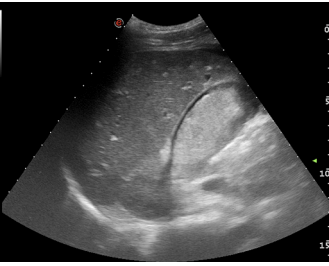

This pericholecystic fluid collection rapidly increased in size on serial FAST examination after 5 min.

He went on to have emergency CT (figure 4) prior to surgery. The patient underwent midline laparotomy with repair of liver laceration and gallbladder. Leakage of bile and blood around the gallbladder was found during surgery. He had an uneventful post-operative course and was discharged on the seventh postoperative day.”